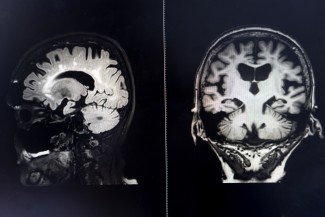

brain MRI for education Dementia Mix type stroke VaD

Seul un neurologue peut poser le diagnostic de démence à l’aide de ces tests, chacun d’eux n’étant ni nécessaire ni suffisant. Par ailleurs, d’autres examens tels que l’imagerie cérébrale par IRM ou une recherche de mutation génétique peuvent conforter ou infirmer le diagnostic. D’autre part, chacune des capacités cognitives évaluée par ces tests peut être diminuée chez le sujet âgé sans que ce dernier ne soit atteint de démence.

Le diagnostic est clinique et fait aujourd’hui appel à des tests diagnostiques performants tels qu’une évaluation neuropsychologique complète des fonctions cognitives, des examens d’imagerie tels que l’IRM et la TEP au glucose qui mettent en évidence les zones du cerveau en souffrance, et enfin la ponction lombaire qui est capable de montrer les signes biologiques de la maladie, c’est-à-dire la présence de dépôts anormaux de protéine amyloïde et de protéine tau.